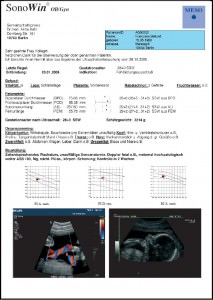

Freely editable examiner’s reporting letter for all medical fields Link

- convenient reporting with integrated images

- freely editable examiner’s letters for all medical fields

- various text modules for fast report writing

- structured reporting for endoscopy, sonography, and echocardiography

- customizable letter template containing logos, tables etc.